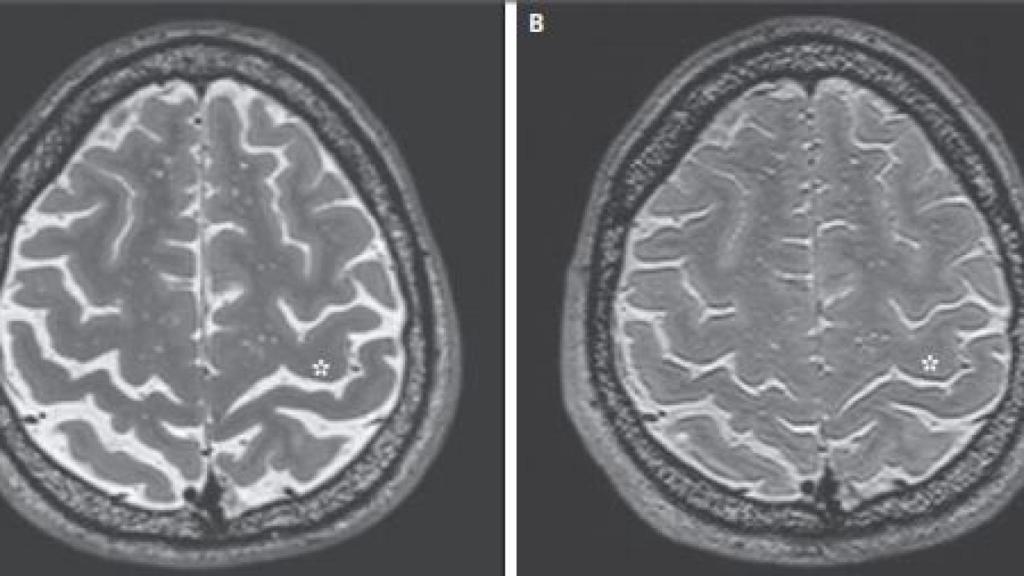

Según las pruebas de neuroimagen realizadas, la mayoría de los astronautas que llevaron a cabo misiones de larga duración sufrieron cambios importantes en su estructura cerebral al volver a la Tierra: sus cerebros se habían desplazado "hacia arriba" dentro de su cráneo, y los espacios destinados al líquido cefalorraquídeo se habían estrechado. Dichos cambios no se objetivaron en los astronautas que realizaron misiones de corta duración.

Así cambió el cerebro de uno de los astronautas. NEJM

Por otro lado, los escáneres demostraron que el 94% de los participantes en misiones de larga duración también sufrían un estrechamiento del surco central del cerebro, el cual separa los lóbulos frontal y parietal. Este estrechamiento también se vio en el 19% de los participantes en misiones de corta duración.